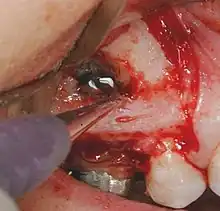

• On choisit un lambeau chirurgical approprié, et on envisage une réclinaison mucopériostée, traumatisante a minima.

• On pratique une ostéotomie en regard de la lésion, on suit la procédure appropriée et le lambeau est replacé et suturé.